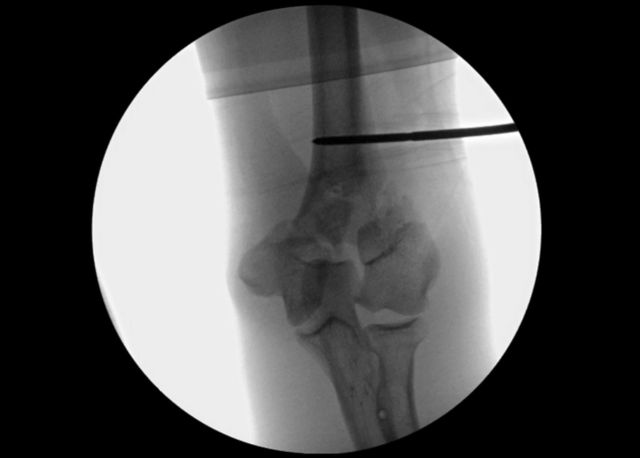

Fig. 3-A.

Anteroposterior c-arm image used to verify that the patient and arm positions allow for adequate imaging of the distal part of the humerus.

Fig. 3-B.

Lateral c-arm image used to verify that the patient and arm positions allow for adequate imaging of the distal part of the humerus.